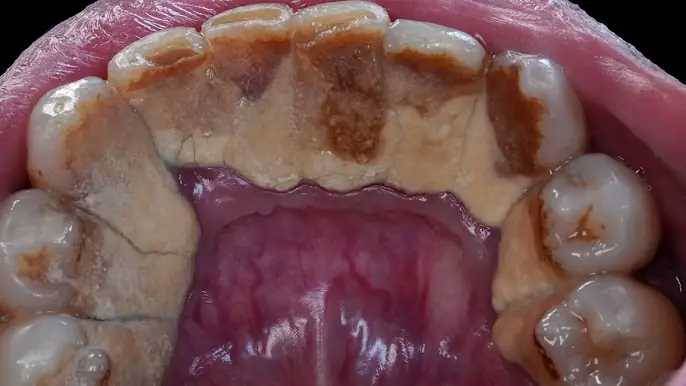

A 45-year-old man visits the dentist with a massive buildup of hardened tartar affecting multiple teeth. Watch as the dentist carefully performs scaling to remove years of deposits, revealing cleaner and healthier teeth underneath. Let’s see the full transformation in the video…